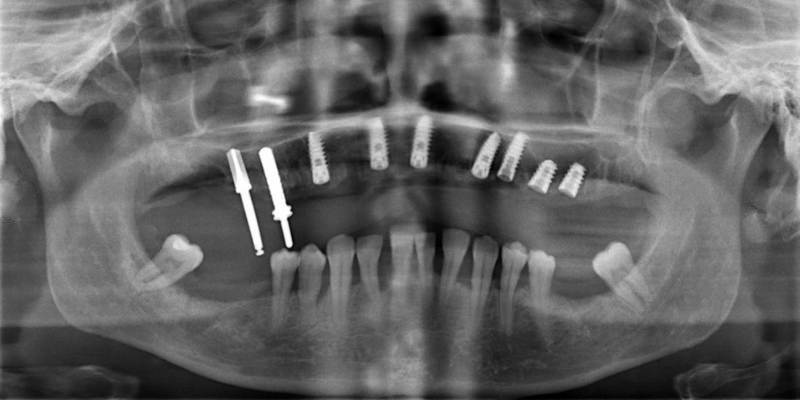

Исследование на рентгене после имплантации зубов

Раздел: Снимки-откровения